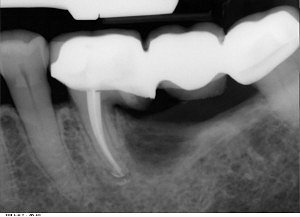

Zaletą amputacji jest

fakt, że zdrowa część zęba pozostaje w kości i po wygojeniu rany pozabiegowej,

może służyć jako filar pod koronę lub most protetyczny. Poniższe zdjęcie

rentgenowskie pokazuje wykorzystanie amputowanego zęba do utrzymania mostu.